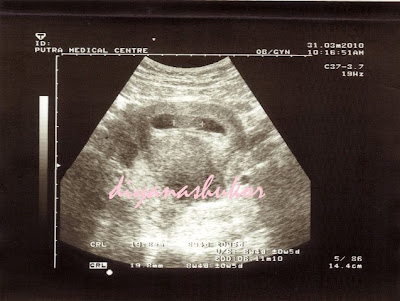

12 weeks

66.0 mm

masa nih dah nampak kepala, badan, kaki dan tangan..

huhu...sgt excited...i'm happy...